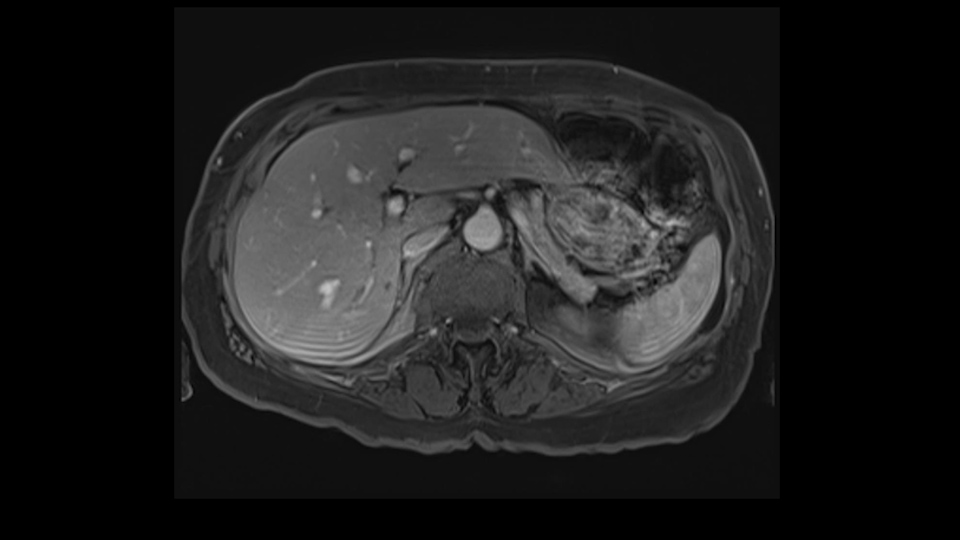

She underwent neo-adjuvant chemotherapy and then had a series of additional investigations and the one that I’m focusing on in more finer detail is an MRI with Primovist and I’ve had the benefit of looking at the report. The main issues are in Segments 5,6, and 7. Three small metastases that remain and the radiologist also comments on the lack of biliary dilatation which was present before; implying that the intrabiliary metastasis somewhere at the origin of the Segment 7 duct, has regressed or been adequately well treated with chemotherapy. That’s probably where the difficult decision making comes in the OR. So from an oncologic point of view, I would plan for a right hepatic lobectomy. The rationale would be that this would include the more peripheral Segment 5, 6, 7 metastases that are obvious but also would take care of the presumed Segment 7 intrabiliary metastasis that does not actually visualize on any of the scans but is assumed to be there with evidence of the duct dilatation which then resolved. One could argue whether we should preserve liver and ignore that duct dilatation that was there before but I think my own preference would be to resect the right lobe and that would certainly include any residual disease in that Segment 7 bile duct and moreover, coming back to do a completion right hepatic lobectomy would be difficult particularly around the porta where this metastasis is presumably still there and even if its quite small.

So when doing a major liver resection, obviously we would focus on a few issues. The first is hepatic parenchyma: is there adequate liver, residual liver and orientation and ratio of the right to left lobe here is pretty normal. It looks like its about 60:40 or 70:30, and because its only a right lobe, I probably wouldn’t do any volumes assuming she has normal liver function which I think she does. The only additional feature of interest is that she has received chemotherapy and one can see the effect of chemotherapy on the density of the liver but again, it doesn’t usually cause significant problems with a short course of neoadjuvant chemotherapy, or liver failure.

So I would then focus on the hepatic outflow because that’s the way we do the operation is by mobilizing the liver. So the vena cava looks quite normal. The right hepatic vein looks quite normal. There are no large additional outflow veins from the right lobe which would generate slowing down moments. The hepatic artery is unremarkable and is not usually an issue we can define the anatomy quite clearly at surgery.